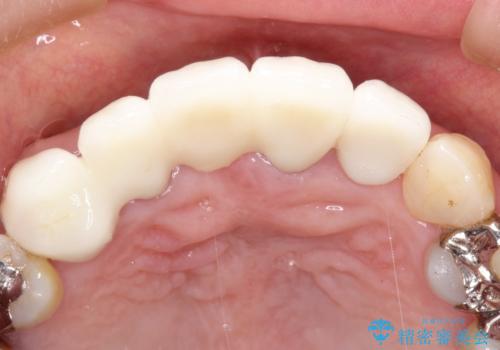

矯正を併用した前歯のセラミックブリッジ治療

- 上顎前歯をきれいにしたいとのことで来院されました。

レントゲンを撮影すると保存が難しい歯がありました。

またがたつきの度合いから歯を1本抜歯して矯正治療を行いセラミックブリッジを装着することで、審美的・機能的改善を行う計画としました。

治療の順序は

①保存不可の歯の抜歯・根管治療

②矯正治療

③セラミックの装着

という流れで行いました。

1年程度の治療期間が必要となりましたが、仕上がりには患者様に満足していただけました。